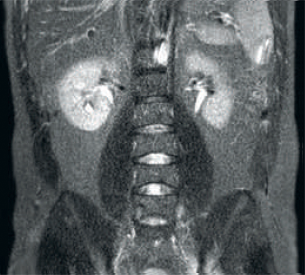

Result: Noisy images using identical scan parameters